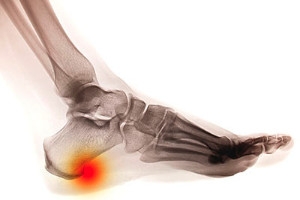

A small growth on the bottom of the heel bone may indicate a heel spur. Patients who have plantar fasciitis may have heel spurs, and this affects the tendon that runs along the bottom of the foot. People who are afflicted with heel spurs often notice heel pain after arising in the morning, and mild relief may be found while walking. The pain may become worse if running or participating in sporting activities, and it is beneficial to rest and elevate the affected foot. It may be helpful to take anti-inflammatory medications which may partially reduce existing pain. If you have the symptoms of a heel spur, it is strongly suggested that you speak to a podiatrist who can recommend the correct treatment options for you, which may include custom-made orthotics.

Heel spurs are formed by calcium deposits on the back of the foot where the heel is. This can also be caused by small fragments of bone breaking off one section of the foot, attaching onto the back of the foot. Heel spurs can also be bone growth on the back of the foot and may grow in the direction of the arch of the foot.

Older individuals usually suffer from heel spurs and pain sometimes intensifies with age. One of the main condition's spurs are related to is plantar fasciitis.

The pain associated with spurs is often because of weight placed on the feet. When someone is walking, their entire weight is concentrated on the feet. Bone spurs then have the tendency to affect other bones and tissues around the foot. As the pain continues, the feet will become tender and sensitive over time.

Heel spurs are calcium deposits that cause bone protrusions on the heel bone. Heel spurs are usually associated with plantar fasciitis, which occurs when the plantar fasciitis in the foot becomes inflamed. Typically, heel spurs don’t cause any symptoms. However, they can produce chronic or intermittent heel pain. Those who have had the condition often describe the irritation as a stabbing pain.

There are risk factors that may make you more likely to develop heel spurs. People who have abnormal walking gaits, run and jog on hard surfaces, are obese, or wear poorly fitting shoes are more likely to develop heel spurs.

The pain associated with heel spurs often decreases the more you walk. However, a recurrence of pain after an extended period of rest or walking is likely to occur with this condition. Those with severe heel spur pain may opt to go the surgical route for treatment. However, more than 90% of those with the condition get better without surgical treatment. If you have a heel spur and want to know if surgery is right for you, you should go to your podiatrist and he or she will be able to conduct a pre-surgical test or exam to determine if you are an optimal candidate for surgery.